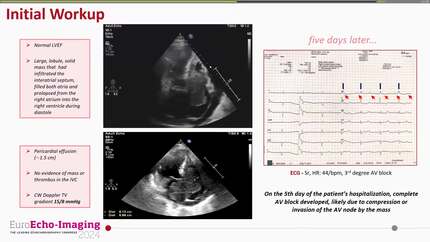

The utility of advanced echocardiographic techniques for evaluation of a cystic cardiac myxoma